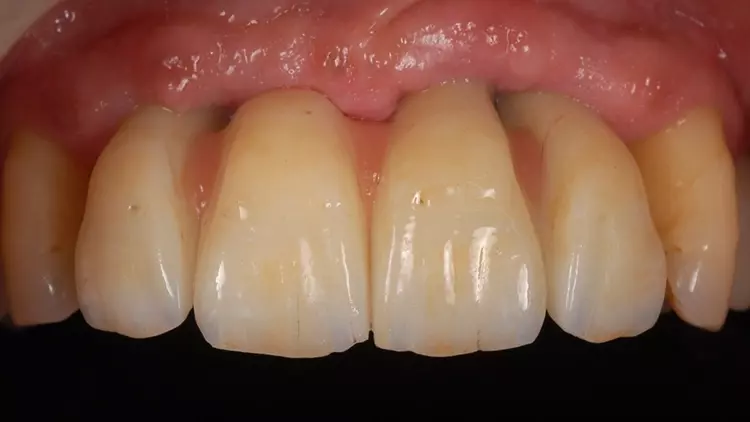

Die Restaurationen fügten sich sowohl klinisch als auch ästhetisch durch ihre spezielle Charakterisierung in die bestehende Patientensituation ein (Abb. 13-15). Auch röntgenologisch konnte eine gute Passform ermittelt werden (Abb. 16).

Der vorliegende Patientenfall beschreibt die Implantatversorgung im Ober- und Unterkiefer-Frontzahnbereich eines älteren Patienten mit einer chronischen Parodontitis und ohne systemische Erkrankungen bzw. ohne eine regelmäßige Einnahme von Medikamenten. Infolge des Attachmentverlusts konnte trotz einer Ridge Preservation mittels Sofortimplantation und einer bukkalen Auflagerung von xenogenem Knochenersatzmaterial insbesondere im Bereich der Interdentalpapillen des Oberkiefers kein ausreichender Weichgewebserhalt in vertikaler Richtung erzielt werden, was auf den Attachmentverlust infolge der Parodontitis zurückgeführt werden kann. Daher war es notwendig, die fehlenden Papillen mittels rosa eingefärbten Zirkonoxids in die Restauration zu integrieren (Abb. 13 und 14).

Der Patient wurde entsprechend instruiert, diese Bereiche täglich mittels Interdentalbürsten zu reinigen. Rezessionen wurden nicht beobachtet, was auf den dicken Phänotyp des Patienten zurückgeführt werden könnte [5]. Trotz der geringen Einschränkungen im Bereich der rot-weißen Ästhetik war der Patient mit dem ästhetischen Gesamtergebnis zufrieden.